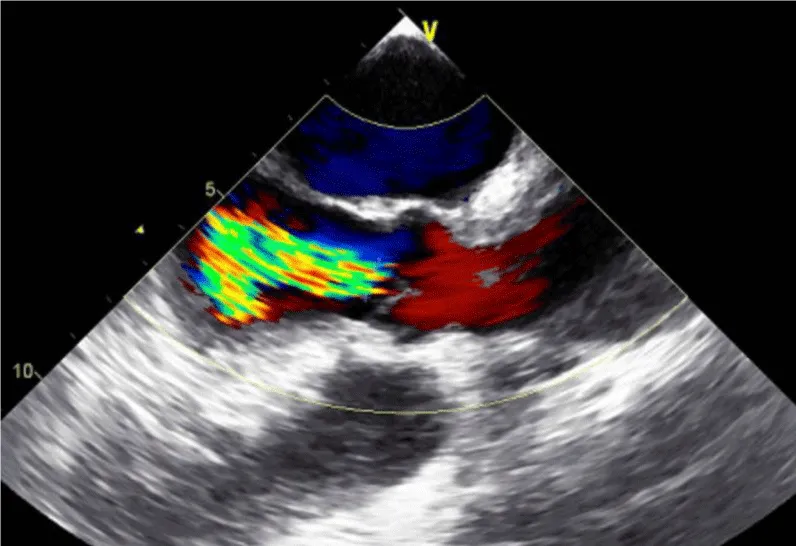

Her initial vital signs upon presentation to the hospital were; blood pressure: 161/76 mm Hg, heart rate: 96 beats per minute, respiratory rate: 27 breaths per minute. Physical exam revealed a cardiac auscultation findings of a grade 2 diastolic murmur which was loudest at the 2nd right intercostal space as well as a grade 2 systolic flow murmur. Cardiac biomarkers were elevated with initial troponin-I of 0.33 ng/mL, peak of 2.28 ng/mL and subsequent down trend. Electrocardiography (Figure 1) showed sinus rhythm with anterior and inferolateral T wave inversion and chest radiograph (Figure 2) was unremarkable. She underwent coronary angiography which revealed normal coronary arteries. The takeoff of the right coronary artery (RCA) was noted to be superior and anterior to its normal position (Figures 3A and 3B). Transthoracic and transesophageal echocardiography (TEE) revealed normal left ventricular systolic function and severe insufficiency of the aortic valve with Quadricuspid morphology (Figure 4A in Diastole, Figure 4B in Systole, Figure 4C Long Axis of the aortic valve). She underwent aortic valve replacement with a # 19mm ON-X mechanical valve. Intraoperatively it was noted that the ostium of the right coronary artery was over the aberrant leaflet. Her postoperative course was complicated by the development of supraventricular tachycardia, posteriorly localized pericardial effusion, severe hemolytic anemia, renal failure and pancreatitis leading to her death eleven days after the surgery.

Figure 4c: Long Axis of the aortic valve demonstrating severe aortic Insufficiency.

The diagnosis of QAV was facilitated by TEE, which revealed the characteristic findings. The short axis views of the aortic valve are optimal for making the diagnosis of QAV. The classic X shaped commissural aortic valve pattern in diastole (Figure 4B) compared to the Y shape of a trileaflet valve is diagnostic (Figure 4D) [3].